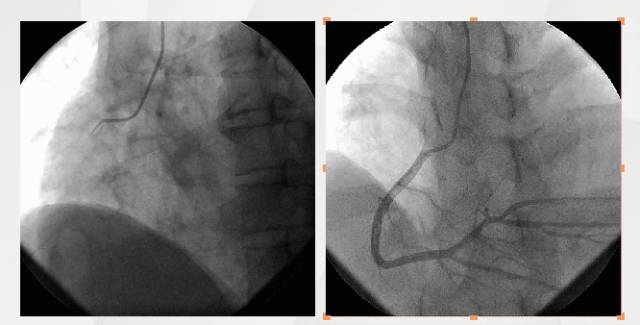

CAG

CAG排除ACS

◆停用抗血小板聚集药物

◆停用低分子肝素钠

◆继续营养心肌

◆改善心功能

◆激素应用

◆全身支持治疗